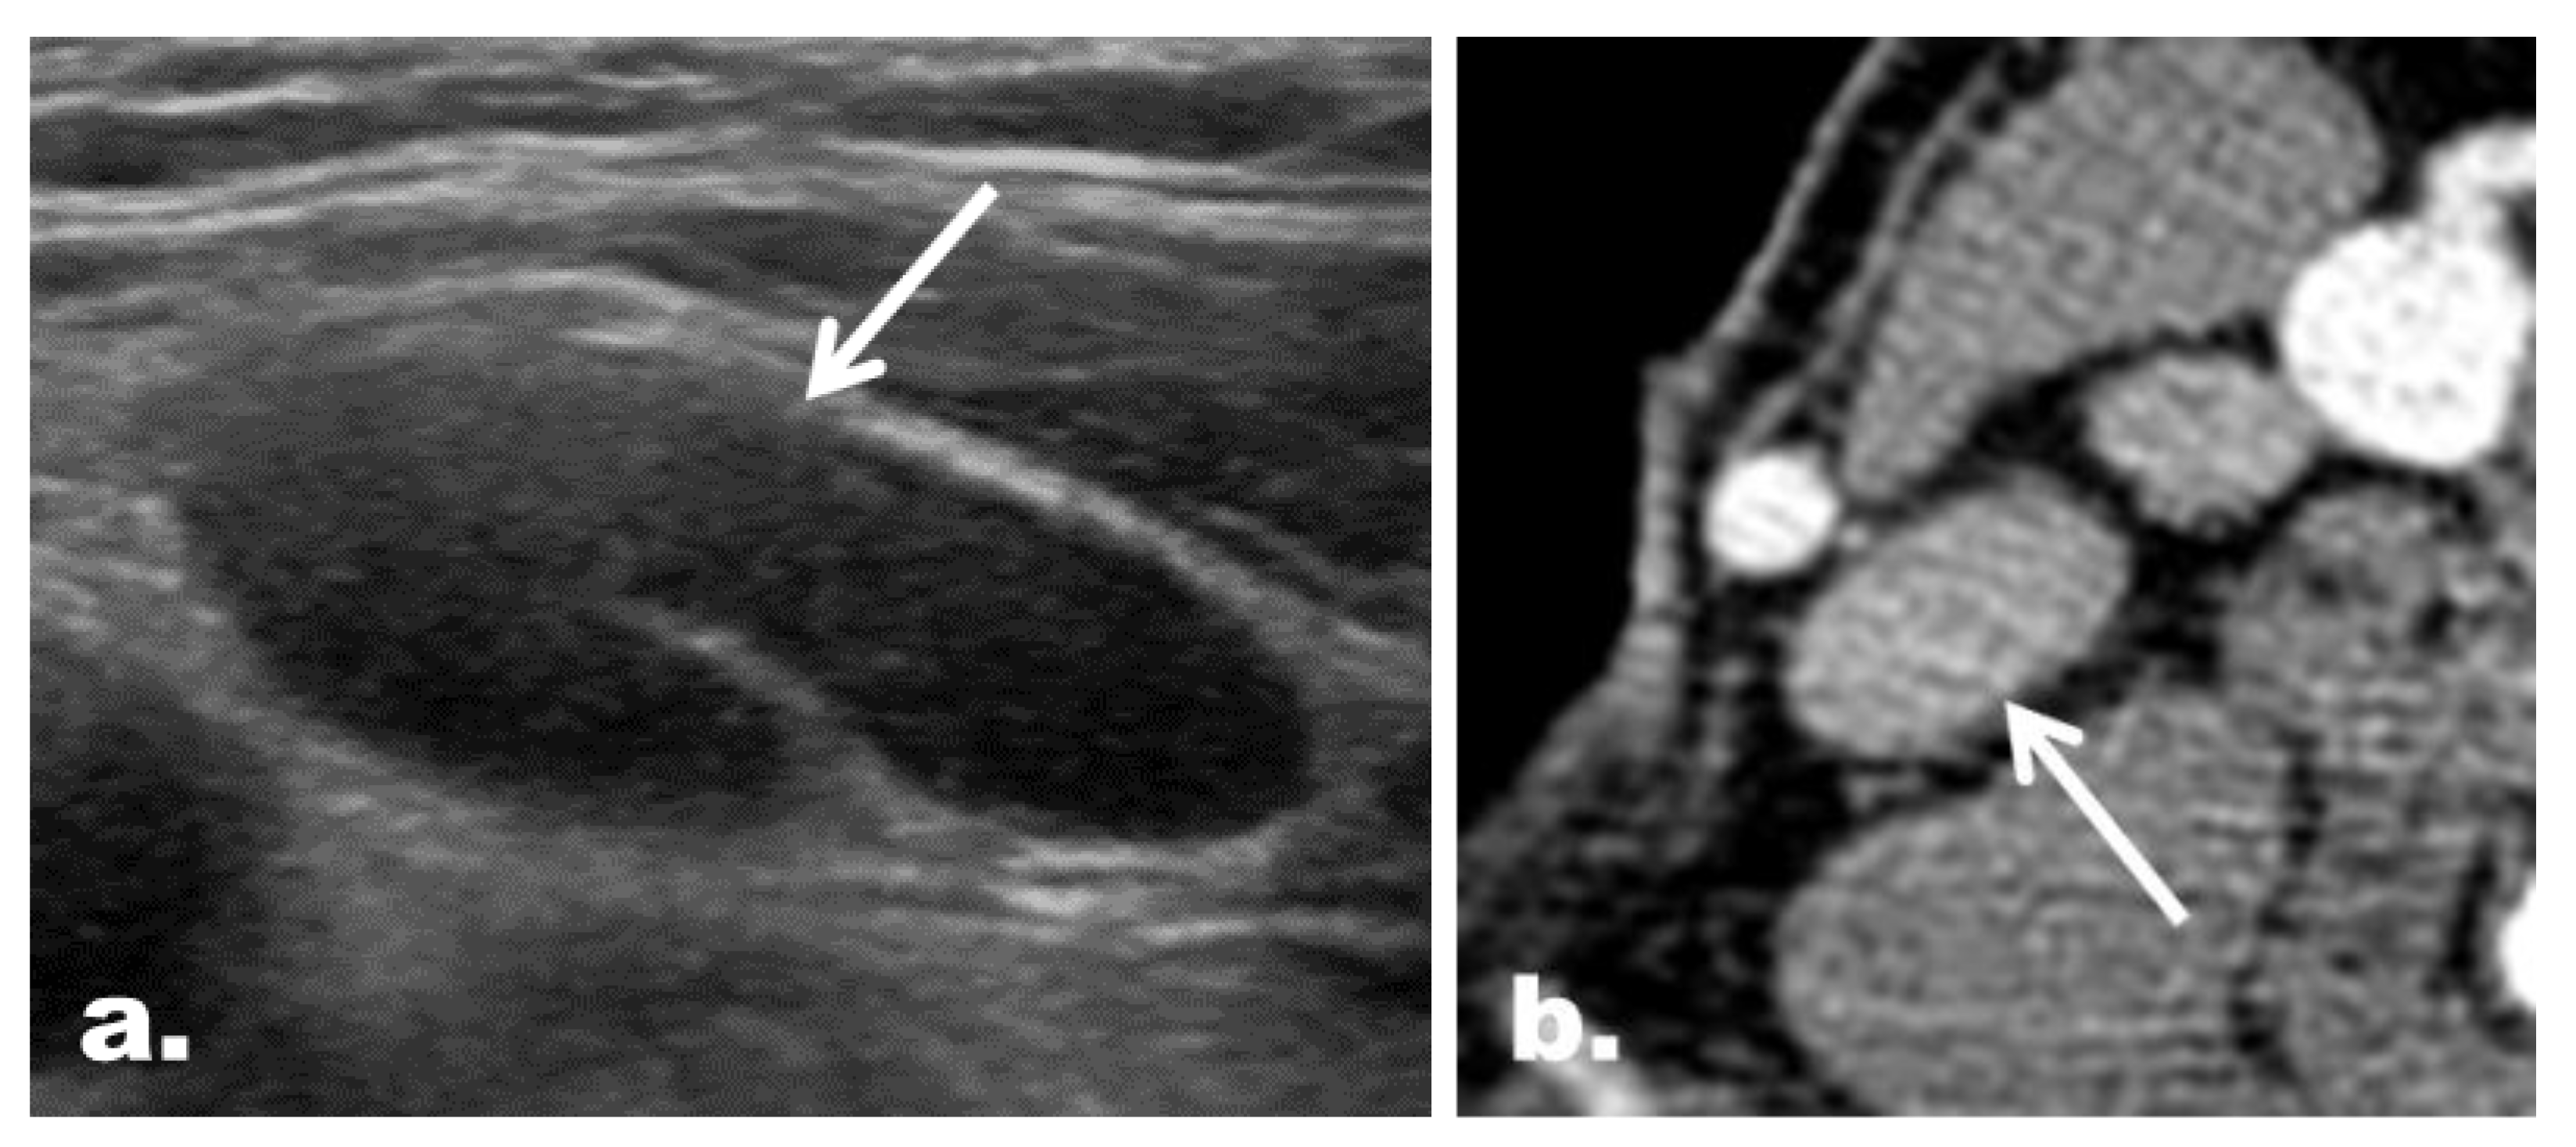

2.5. CT Imaging Features in the Reclassified Cases